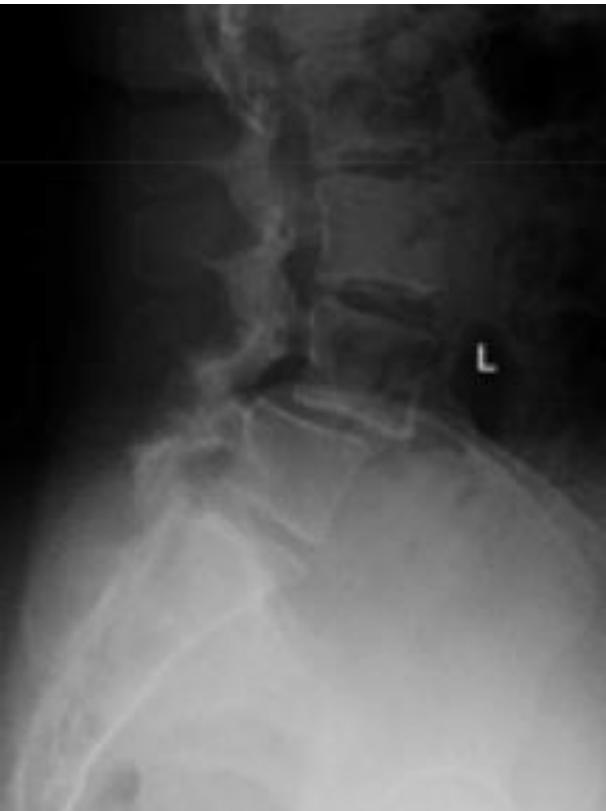

Degenerative Spondylolisthesis

- Definition: Common degenerative condition characterized by subluxation of one vertebral body anterior to the adjacent inferior vertebral body with intact pars

- Demographics: Most common in females over 40 years of age, at the L4-5 level

- Diagnosis: Lateral radiographs; flexion and extension lateral lumbar radiographs can identify degree of instability